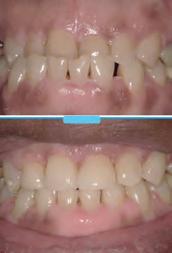

New Solutions For Dentures and Dental Implants

Dentures are a good replacement option for patients who are missing all of their teeth, but only if they fit well.

Why Are My Dentures Loose?

Impact on the bone by continuous hitting and pressure of a denture against the jaw every time you eat can make the bone underneath the denture go away. This causes the denture to become loose and slip. It may create the need for using paste or other means to hold the denture in place. Slipping dentures can make eating certain foods very difficult for patients. This happens most often with lower dentures.

How Can Dentures Fit Well For a Long Time?

Dental implants can be placed under the denture. Implants have offered the possibility of fully replacing teeth for over 30 years and are very safe and effective. When you make the denture stable by “snapping” it onto dental implants, you can provide a better level of comfort for the denture-wearer, and create new strength for eating the foods patients love.

Dental implants are very much like your natural teeth. They are quite easy to get used to, and they can reduce the amount of stress to the bone and jaw by helping provide an anchor for support. The implant acts as a natural root to help prevent additional bone deterioration and helps to deliver long lasting function.

Does Every

Denture-Wearer Qualify?

This depends on the amount of bone loss that has already taken place. If the denture has been in place for many years and the ridge of bone under it is very thin, you may need to have a special scan done to decide if you are a candidate for the procedure. This scan will also look for any other defects that may be present to make sure you are healthy. Since implants are meant to last for a very long time, your health and wellness are important to the outcome.

How Long Does a Patient Have To Go Without Teeth?

Never. The denture is fitted to the implants, the same day the implants are placed. Typically, you are back to normal or better eating by day two or three.

Do Dental Implants Hurt?

Most patients have little to no dis-

comfort. The surgery is done in one day, typically in just a few hours. There are sedation options available for this procedure for those patients who want to relax through the procedure.